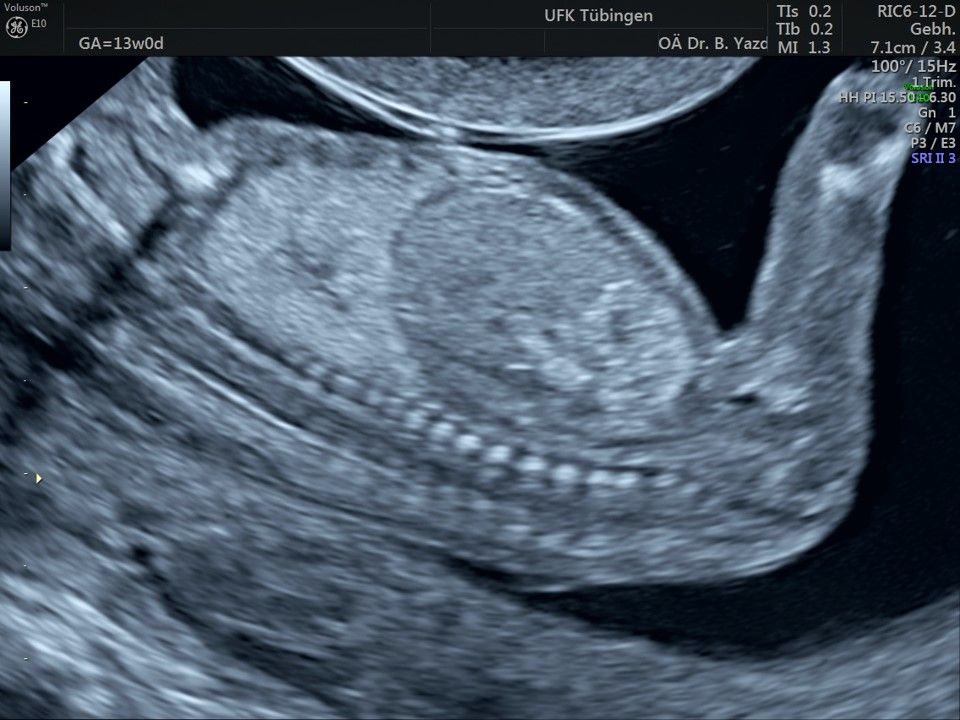

Im Rahmen des Ersttrimester-Screenings untersuchen wir die Organe des Feten mittels Ultraschall. Dabei machen wir auch gerne ein Bild für Sie.

Obwohl der Fet zu diesem Zeitpunkt erst zwischen 5 und 8cm groß ist, lassen sich bereits etwa die Hälfte aller schwerwiegenden Fehlbildungen erkennen bzw. ausschließen. Sollten wir eine Auffälligkeit sehen, werden wir mit Ihnen den Befund und das weitere Vorgehen ausführlich besprechen.

Fetale Anatomie

Das Ergebnis der Ultraschalluntersuchung ist wegweisend. Dabei wird der Fet vermessen, die Organe werden untersucht und die sonographischen Marker zur Risikoberechnung für Chromosomenstörungen werden beurteilt. Das sind: die Nackentransparenzdicke, Nasenbein sowie der Blutfluss in der rechten Herzhälfte und im Ductus venosus, einem Gefäß in der Leber des Feten.